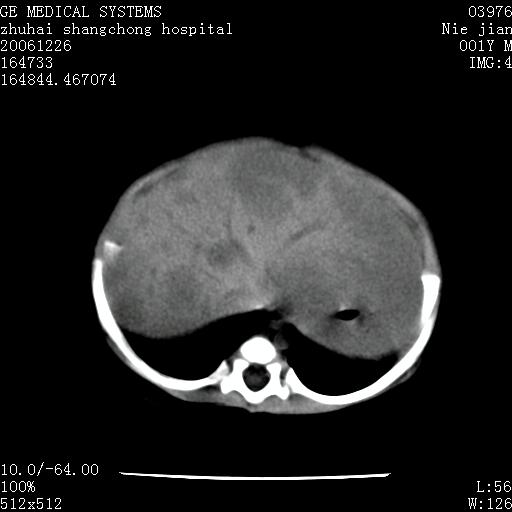

3个月婴儿腹胀来看。

肝各叶比率失调,明显增大,实质内大量脂肪侵润。另:左侧肾上腺区较大类圆形低密度肿块,左肾明显受压 下移。多考虑:1 左侧肾上腺神经母细胞瘤!2 肝弥漫性损伤!

肝各叶比率失调,明显增大,实质内见多发团块状低密度灶。另:左侧肾上腺区较大类圆形肿块,左肾明显受压 下移。多考虑:1 左侧肾上腺神经母细胞瘤!2 肝脏多发转移!

鉴别诊断:肾母细胞瘤,好发1-3岁,肾母细胞瘤是发生在肾脏,又称肾胚瘤,肾脏本身增大。而神经母细胞瘤也称成神经细胞瘤,好发1-2岁,多发生在肾上腺髓质。肾脏本身表现受压向下移位。

【影像特征】

1、肝明显增大,肝弥漫性低密度灶。

2、肾上腺区见类圆形肿块,其内密度不均,见片状偏高密度。

1、肝弥漫性病变,考虑急性肝炎致广泛脂肪浸润可能性大。

2、肾上腺区占位,假性肿瘤?肾上腺血肿(感染所致)?

1、关键着眼点:肝脏弥漫性病变内有没有走形的血管,仔细看部分低密度内有血管影(要有增强扫描作为证据就好了),说明并非肿瘤样病变,而是脂肪浸润。即可能不是转移瘤或原发肿瘤,低密度的形态上看,是片状,也不像肿瘤。

2、儿童肝炎最常见的是感染,有时食入性损害或药物也可致肝脏炎症,肝炎致大空泡型脂肪变性,是一种无痛性疾病,无症状,病因有营养异常、代谢性疾病、药物及病毒感染。所以脂肪变性与感染有关。

3、肝炎的结局是肝硬化,而恰恰一年后复查,已有肝硬化表现。肿瘤一般那会消失,那叫奇迹。

4、肾上腺出血也可见于败血症及感染,通常包块在数周内消失,ct表现包块内有偏高密度,可能是亚急性血肿的表现。假性肿瘤即腹部肠管积液、扩张血管及邻近结构的伪像。自然会消失。

5、因此,感染可以贯穿一切,解释一切。肿瘤自然消退?可能吗?那些应要无道理的创造奇迹的事情会那么容易发生吗?